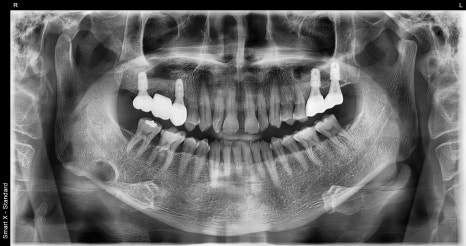

Left photo: panoramic X-ray taken at the patient’s first visit.

Right photo: initial intraoral photo showing the condition of the gums and teeth in the molar area.

The large molar at the very back had already been missing at the first visit, and the molar in front of it had severe periapical inflammation.

In addition, the small molar was severely mobile, so both teeth were extracted and replaced with implants, while overall gum treatment was also performed to establish the treatment plan.